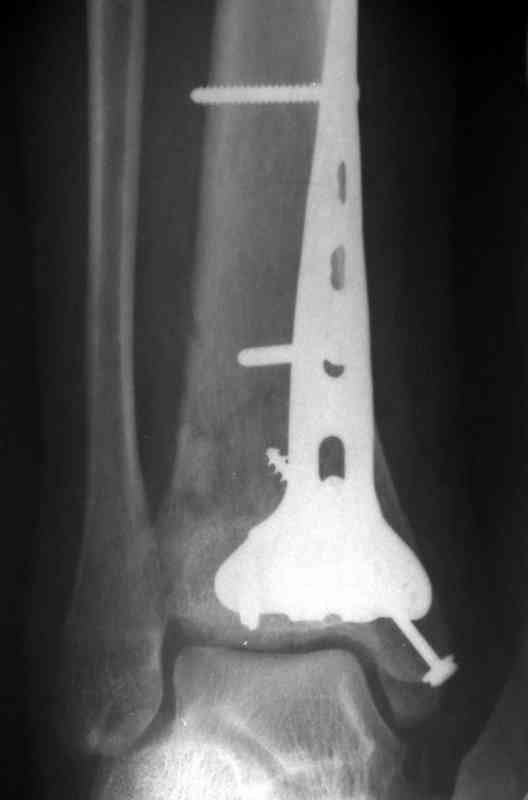

На рентгенограммах типичный перелом пилона по типу С-3. есть опыт до 100 открытых опреаций у нас в клинике. 20 примерно в год. Принцип один -все внутрисуставные переломы нуждаются в открытой репозиции и внутренней стабильной фиксации. При поступлении КТ не надо, так как получается только нагромождение костей. Истинной картины нет. Главное восстановить длину малоберцовой кости - это ключ к успеху. При поступлении меньше всего надо думать о сосудистых расстройствах, т.к. сама операция и репозиция даже сначала частичная даёт улучшение сосудитых нарушений. Причём очень быстро. Операция в 2этапа. При поступлении доступ позади наружной лодыжки, причём обязательно. После этого репозиция малоберцовой кости и фиксация пластиной 1/3 трубки под винт 3,5. Дренаж и любой аппарат наружной фиксации. Затем после спадения отёка на 5-7-10 день аппрат снимается и дугообразный разрез спереди от медиальной лодыжки 10-12 см. Главной чтобы расстояние между 1 и вторым разрезом было не меньше 7-8 см. Тогда не будет некрозов лоскутов. Таранная кость используется как матрица на неё укладываются отломки и фиксируются пицами. Ренг-контроль. Отломки лежат все отдельно, но ничего не высыпется. При переломах С-3 всегда нужна костная пластика (из крыла). Фиксация пластиной лист клевера простой или LCP. Гипс не нужен. Дренаж до 48 часов. Операция длится 3-4 часа обязательно без жгута. Посылаю примерно такой же случай.

Посылаю результат лечения предыдущего больного через год.

С уважением Дрягин